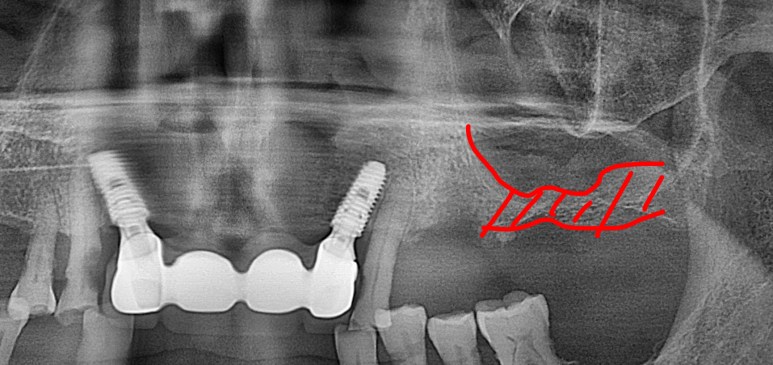

2025년 9월 11일 첫 내원 시 촬영한 파노라마 방사선 사진입니다.

진단 결과 하악(아래턱) 전치부 치아가 모두 상실되어 심미적인 문제는 물론, 앞니로 음식을 끊어 먹는 기본적인 저작 기능이 불가능한 상태였습니다. 또한 좌측 상악(위턱) 어금니 부위 역시 치아가 상실되어 있어 종합적인 보철 수복이 필요한 상황이었습니다.